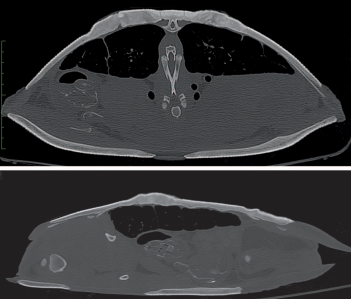

Sagittal and transverse CT images of the same penetrating lesions in an Aubry’s flapshell turtle (Cycloderma aubryi) shown in Figure 1, from followup CT on 4 August 2021, 29 months after ending treatment, showing healed shell lesions with bone regrowth.